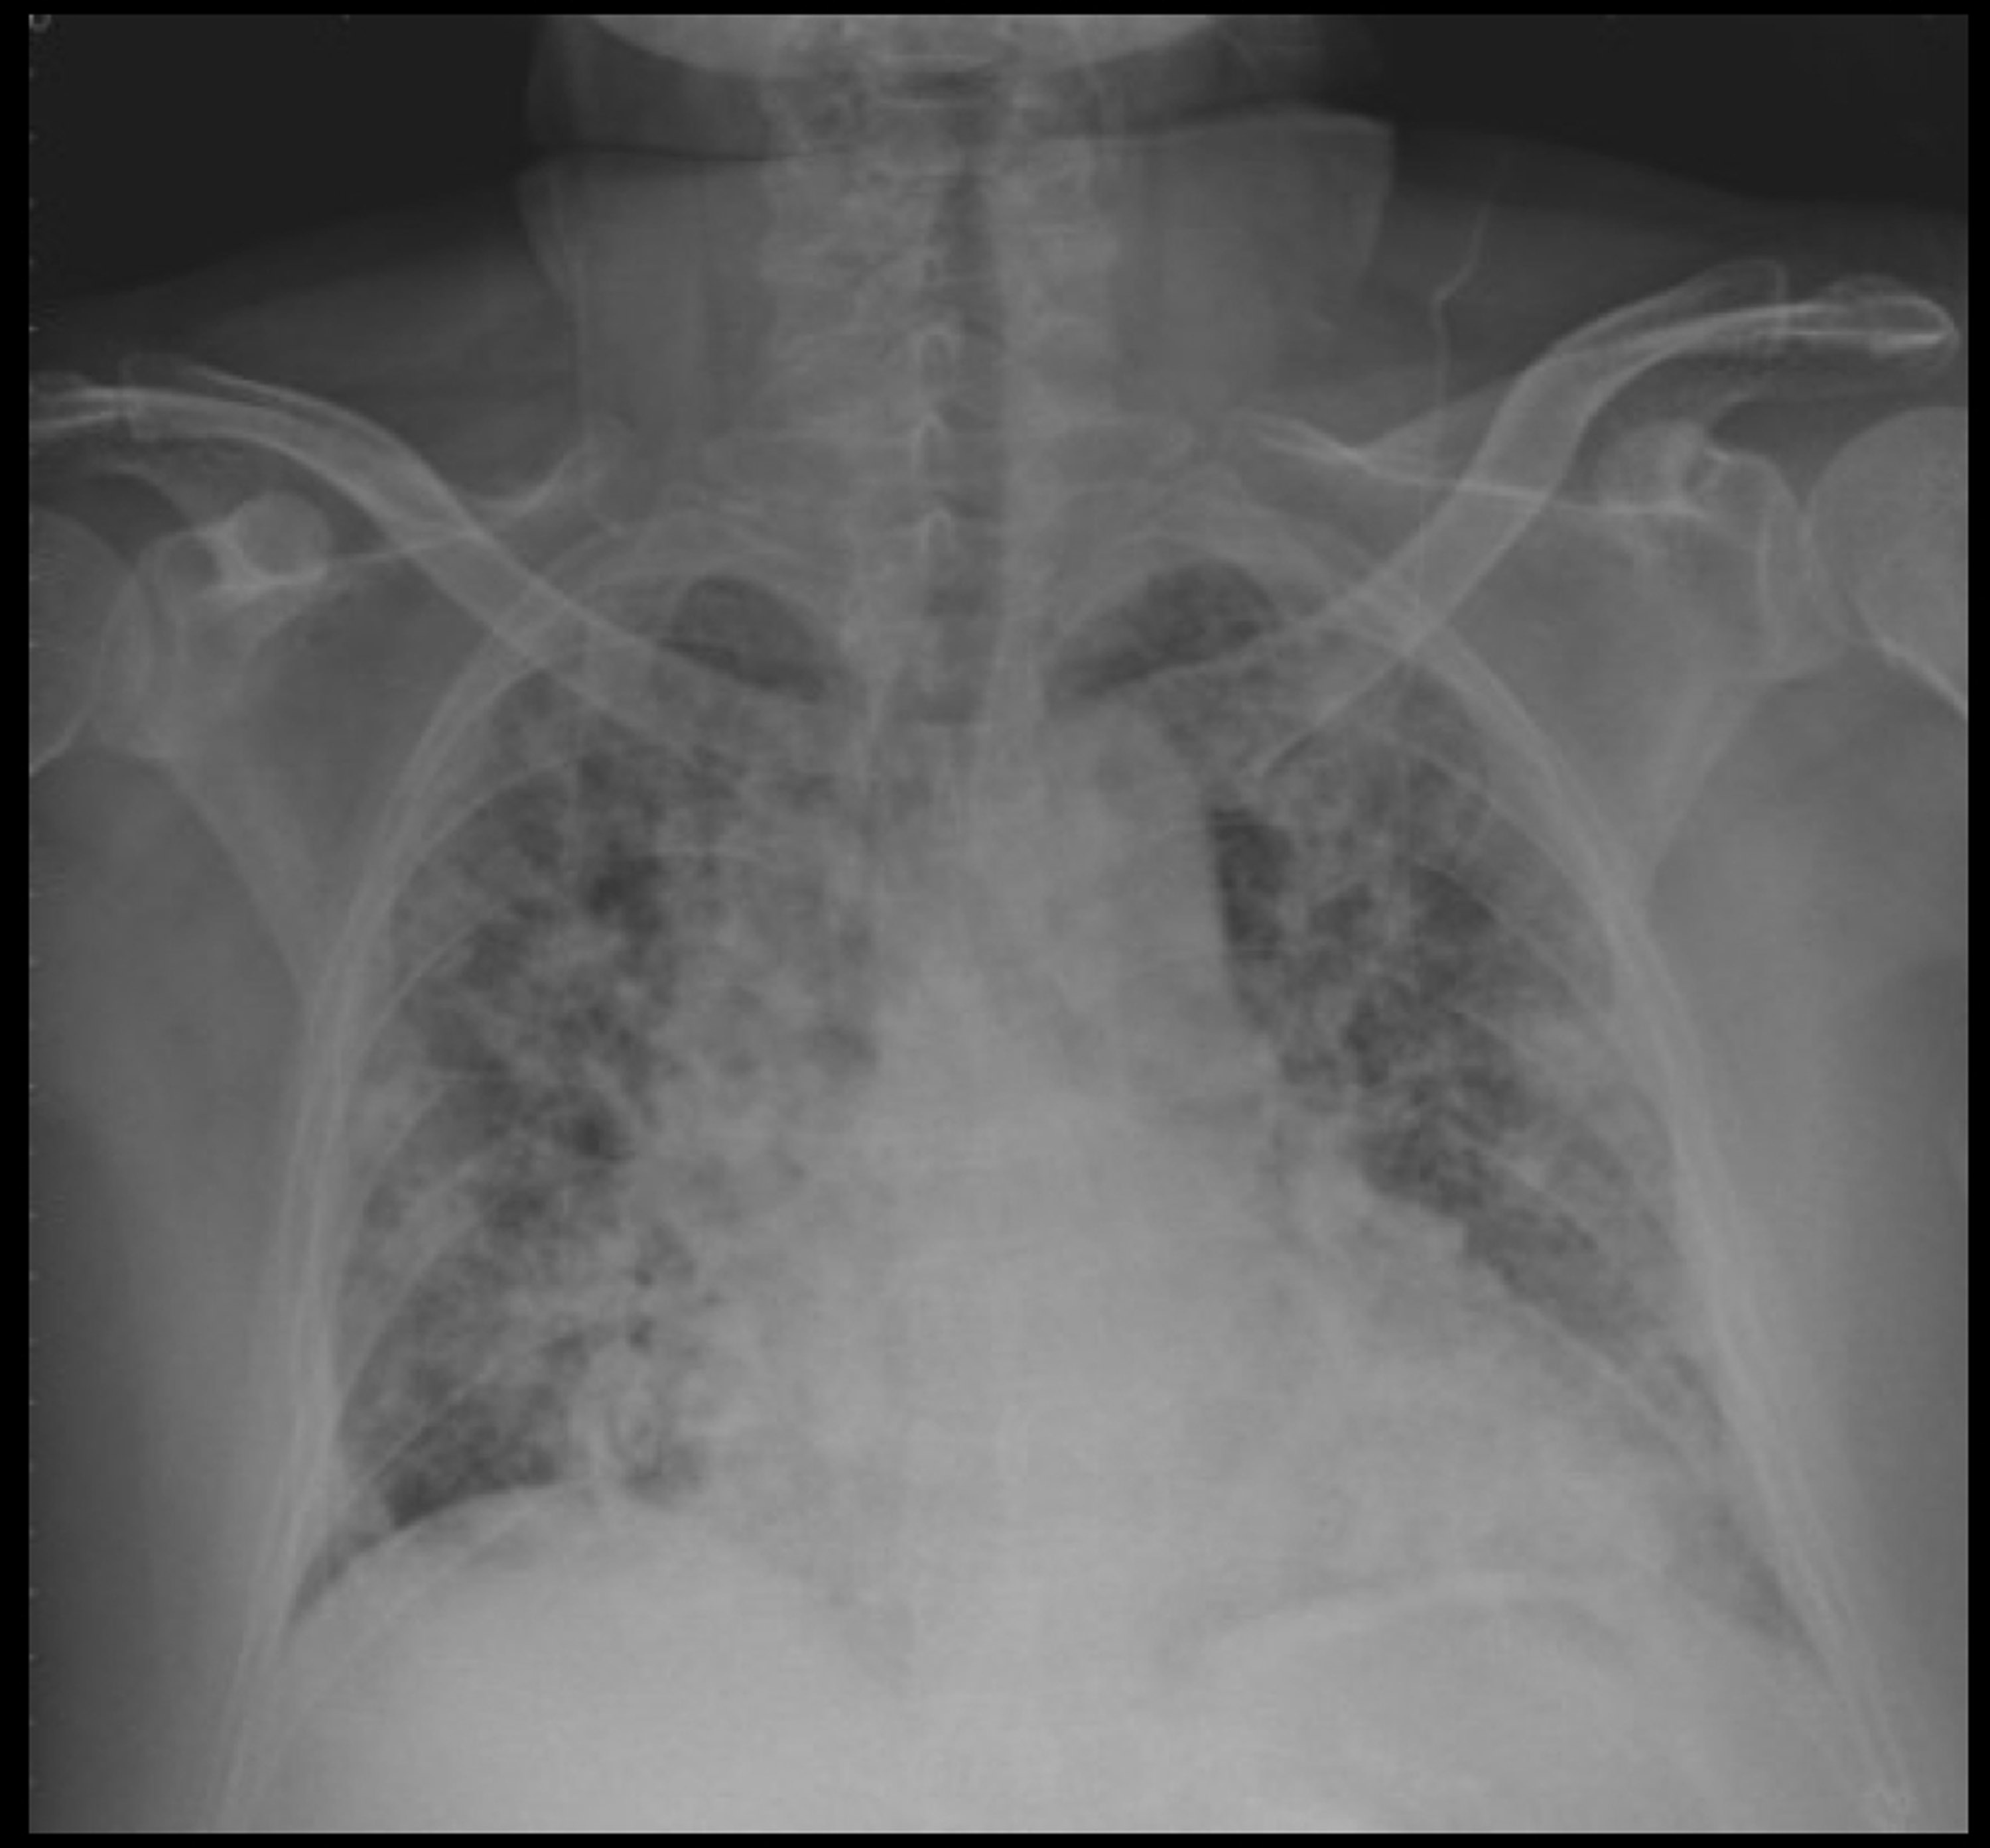

吸入性嗆傷 Heho健康

吸入性呛伤会永久伤害呼吸道 做好这3点保护肺部 每日头条